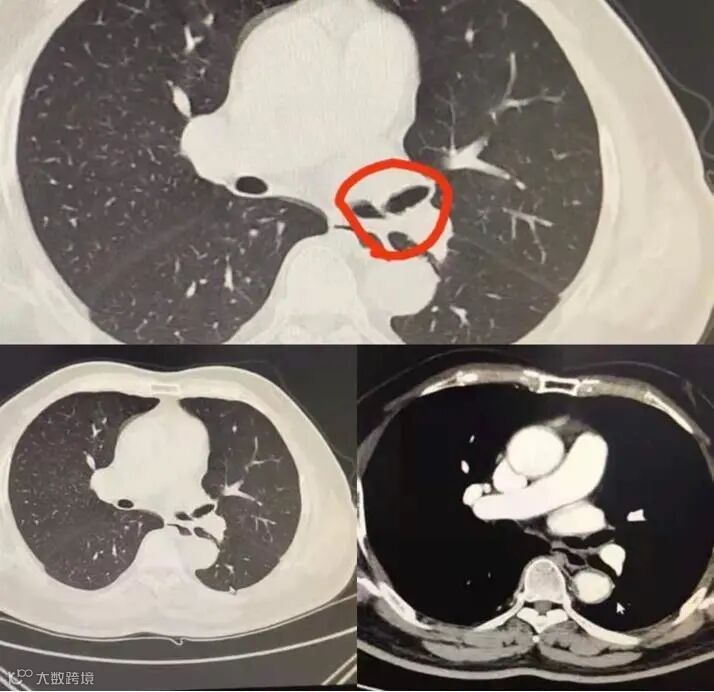

76岁的刘大爷(化名)反复咳嗽、咳痰已经有7个多月了,严重甚至咯血,期间曾多次在当地诊所治疗,却未能根治,咯血仍反反复复。为了查清原因,刘大爷来到了北海市人民医院检查,胸部CT检查发现左主支气管变窄,医生考虑是有异物存在,在进一步做了支气管镜检查后,终于发现反复咯血的“元凶”——左主支气管包裹了一块像鱼骨一般的异物!

查明病因后,呼吸内科内镜小组经充分评估病情及适应症,决定拟先行“经支气管镜异物取出术“,取出异物后再行氩气刀将残存的肉芽进行热消融处理,修复气道粘膜。在做了大量的术前准备后,手术开始。

由于包裹时间太长, 大部分异物已被血管丰富的肉芽固定,而且触碰易出血,黄振杰使用异物钳通过反复调整方向,终于取出一条长度为1.5cm的鱼骨异物!